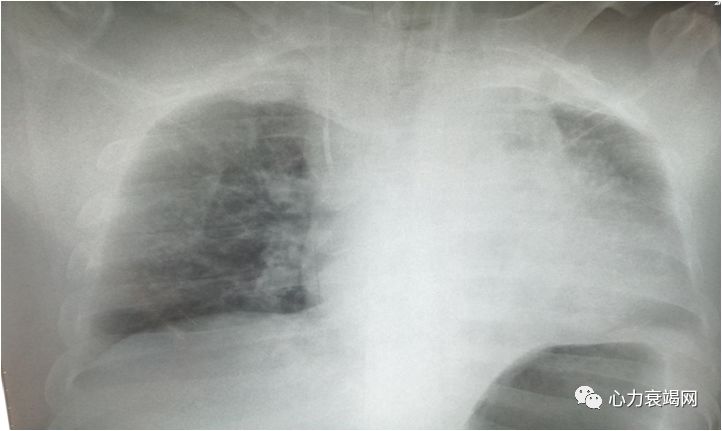

(ECMO第1天,9.29)

EF20%

课件提供资料:本例患者以压榨性胸痛发作3天于9月29日转入,入院时Bp 84/46mmHg,心电图示S1QⅢTⅢ、V5导联R/S<1,cTnT 0.144ng/ml,NT-pro-BNP6177.7 pg/ml,D二聚体11.68mg/L,Lac 7.7mmol/L,入院考虑冠心病心梗,肺栓塞?肺癌?初步治疗后(不详)胸闷胸痛无好转,血压持续低,心电不稳定,PaQ2降至87mmHg,PaCO2及乳酸升高,即予ECMO、液体负平衡、抗凝抗血小板并加予”左西孟旦”治疗,逐渐血压上升,氧合改善,一周后转普通病房治疗,10月9日又突发胸闷气短,后续治疗未列出。入院前淋巴结活检提示:转移性低分化腺癌,CTPA示肺栓塞。